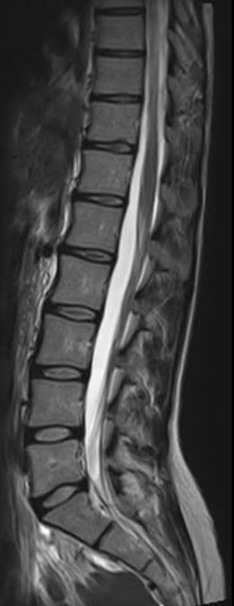

避免不必要的脊柱手术

- 颈椎影像 — 细致的亚专科复查

- 椎管狭窄 — 了解您的影像结果

- 脊椎滑脱 — 结合临床背景的亚专科判读

- 椎间盘膨出 — 专家影像分析

椎间盘突出 · 是否需要手术?

- 在临床背景下审阅椎间盘突出影像

- 神经压迫评估

- 手术合理性明确化 — 基于循证医学

- 骨科影像专家分析

腰椎

脊柱手术复查